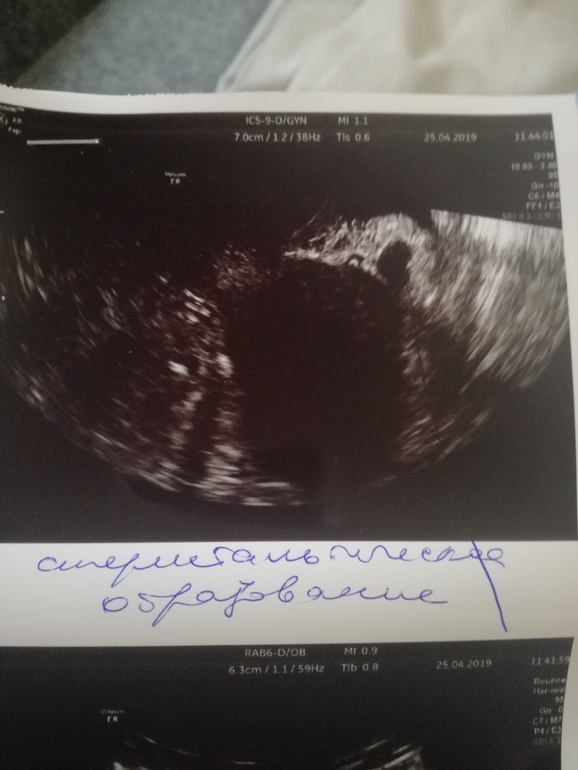

УЗИ, всё плохо?

Девочки, пожалуйста , скажите что здесь насмотрели у меня . Глаза на мокром месте, одна труба левая , правая удалена